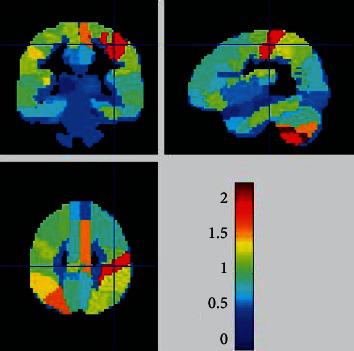

Twenty-seven HIV-infected patients and 14 healthy controls were enrolled in our study. Each set of BRAVO images was postprocessed using DPARSF3.1 to coregister all brains on the MNI template, and volume extraction of 90 brain regions was performed using custom-designed code. The machine learning method was performed using PRoNTo2.1.1 toolbox. The differences in brain volume between the HAND and non-HAND groups were analyzed.

本研究纳入了 27 名 HIV 感染患者和 14 名健康对照者。使用 DPARSF3.1 对 BRAVO 图像进行后处理,将所有大脑配准到 MNI 模板上,并使用定制设计的代码提取 90 个脑区的体积。使用 PRoNTo2.1.1 工具箱进行机器学习方法。分析 HAND 和非 HAND 组之间的脑容量差异。